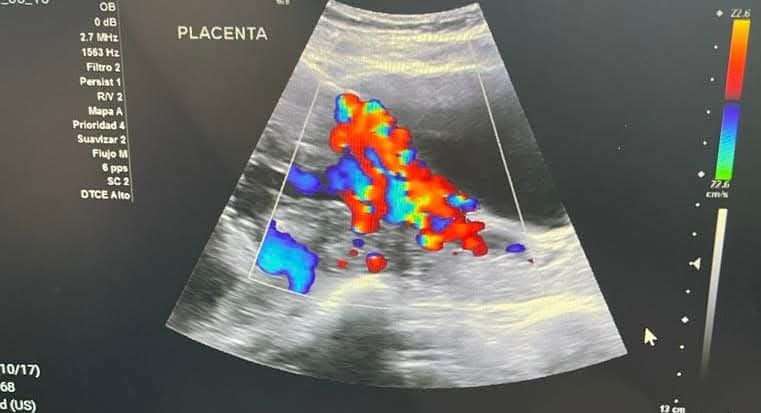

Chacón Lechuga indicó que la mayoría de los casos atendidos son por acretismos placentarios en sus tres niveles: acreta, percreta e increta, es decir, que la placenta está adherida de una manera anormal a la matriz, a otros órganos y a los vasos sanguíneos, lo que puede provocar una hemorragia severa.

Señaló que a nivel mundial, una de cada cuatro personas con esta patología fallece, pero que desde junio de 2018, en la ciudad de Chihuahua no se ha registrado una muerte materna directa por causas obstétricas propias del embarazo en el hospital.